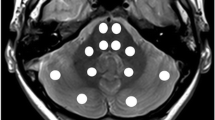

Two observers independently determined regional T1 relaxation times by manually drawing the largest possible region-of-interest (ROI) for a particular structure using conventional radiologic image processing (IntelliSpace Portal; Philips, Best, the Netherlands). They evaluated the following locations: nucleus caudatus, putamen, globus pallidus, thalamus, nucleus dentatus, frontal white matter, occipital white matter, brainstem at the level of the fourth ventricle just below the pons and the bulbus oculi (Fig. 1). To determine the intra-rater variability, the observers assessed the same region in the left and right hemisphere; no differences were expected according to previous studies [16, 28]. The mean and standard deviation of the T1 values per ROI were determined.